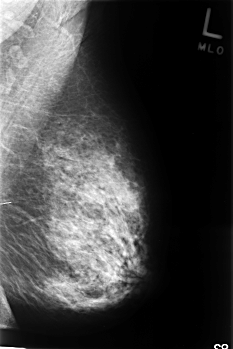

C_0350_1.LEFT_CC

LEFT_CC LINES 4632 PIXELS_PER_LINE 3080 BITS_PER_PIXEL 12 RESOLUTION 50 NON_OVERLAY